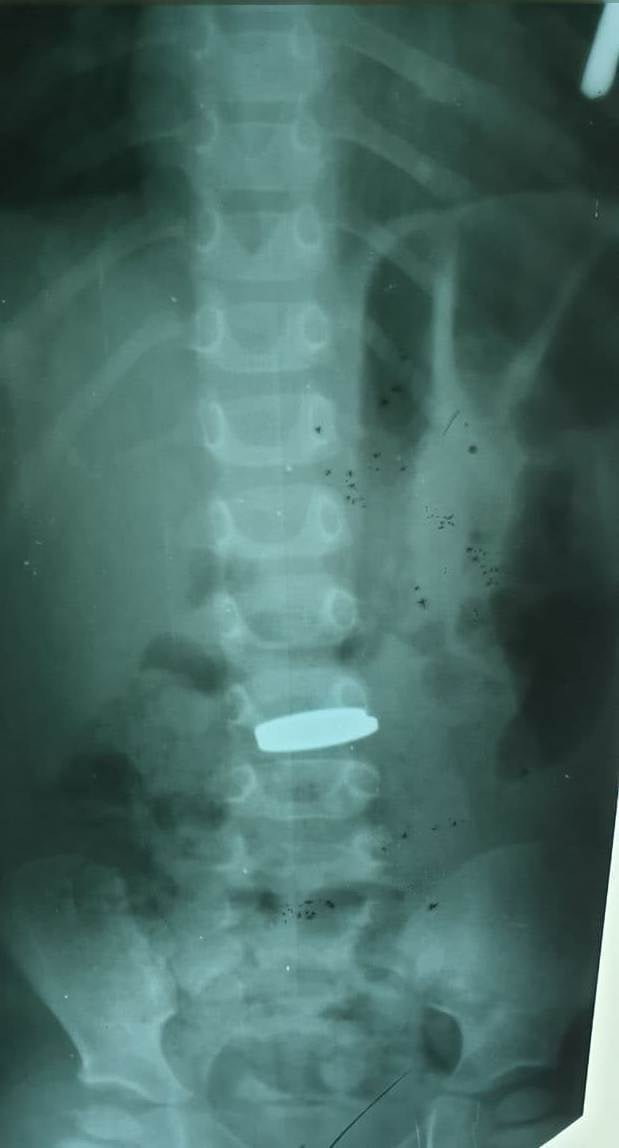

"Провели обзорную рентгенографию, на которой было обнаружили рентгенконтрастные инородные тела в желудке. Под общим обезболиванием провели захват и удаление инородных тел из желудка. Ребенок в удовлетворительном состоянии. "Вот так и зарабатываешь валюту на жизнь с процентами", - написал врач.